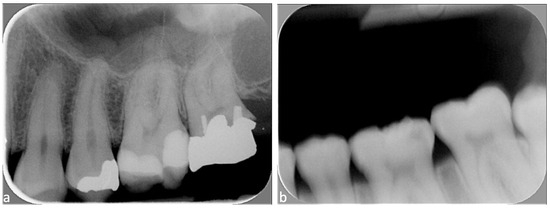

| Centering the cone with or without rectangular collimator | Image outline Tooth fully visible | Complete image outline; borders not cut No truncated image | Incomplete image outline; image cut without consequences on diagnosis | Incomplete image outline, image cut, with consequence on diagnosis |

| Centering of the digital plate | Ratio of maxillary and mandibular quadrants (visibility of teeth and alveolar crest at vertical level) | 50–50% ratio: image well centered vertically (maxillary and mandibular teeth each cover 50% of the image) | 40–60% ratio: image moderately centered vertically (one quadrant covers more than half of the image, alveolar bone visible on both quadrants) | Image not vertically centered (one quadrant covers more than 60% of the image, alveolar bone of opposite quadrant not visible) |

| Distal contact points (between canines and the 2nd lower molars) | 4 distal contact points are visible | 3 distal contact points are visible | <3 distal contact points are visible | |

| Correct bite on the film-holder | -- | Yes Upper and lower quadrants in contact with film-holder | No One quadrant without contact with film-holder | |

| Superposition of enamel (horizontal angulation) | Superposition of enamel on the contact points | Superposition <1/3 of enamel width | Superposition between 1/3 and 2/3 of enamel width | Superposition >2/3 of enamel width |

| Image contrast | Correct image contrast | -- | Yes | No (too bright or too dark) |

| Artefacts | Exposure to ambient light, presence of foreign object or vertical stripes | -- | No Or minimal without consequence on diagnosis | Yes With consequence on diagnosis |

| Intact digital plate, without traces of scratches, folds, or other | -- | No Or minimal without consequence on diagnosis | Yes With consequence on diagnosis | |

| Overall X-ray quality | Overall quality | Excellent overall quality | Acceptable quality; minor faults/errors | Major error; diagnosis made difficult |